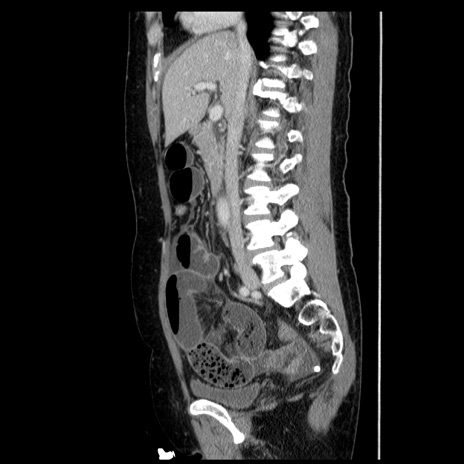

症例6(矢状断像)

【症例】50歳代女性

【主訴】下腹部痛

【現病歴】本日朝より下痢2回あり。 昼食を食べた後、嘔吐3回、下腹部痛認め、症状軽快せず、当院救急搬送。

最終食事:本日昼(生ものなし)。 昨日の夜、刺身を食ぺたとのこと。周囲に同様の症状の者なし。普段、排便は毎日あるとのこと。

【既往歴】卵巣癌術後(8年前に当院で卵巣摘出)

【身体所見】 意識清明、腹部:平坦、腸蠕動音→、やや硬、下腹部自発痛・圧痛あり、反跳痛あり、筋性防御なし。

【データ】WBC 16000、CRP 0.01